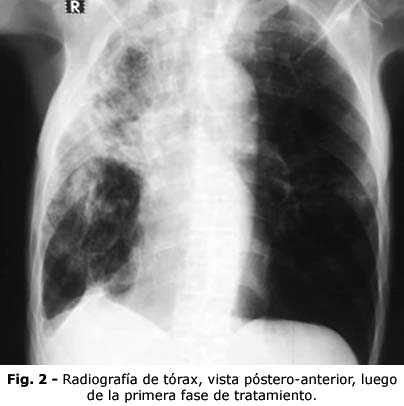

En el cuadro actual, los exámenes hemoquímicos no mostraron alteraciones. En la radiografía de tórax, vista póstero-anterior (Fig. 1) se observó una imagen de opacidad heterogénea, aspecto inflamatorio, con tendencia a ser fibroexudativa que ocupaba los dos tercios superiores del pulmón derecho, y una imagen de aspecto inflamatorio, en los dos tercios inferiores del pulmón izquierdo.

Los síntomas de TB pulmonar son a menudo inespecíficos, o pueden estar ausentes en un 5 % de los casos. La tos, hemoptisis y pérdida de peso son también síntomas del cáncer pulmonar.(11) Algunos patrones radiológicos atípicos de la TB pulmonar, se confunden con neoplasias, en el 3,5 % al 4,5 % de los casos.(3,12) El índice de sospecha de TB pulmonar fue alto con la radiografía del paciente; existía una afectación extensa, para pensar solo en una neoplasia de pulmón, que pese al gran tamaño, no tenía evidencias de metástasis extratorácica.